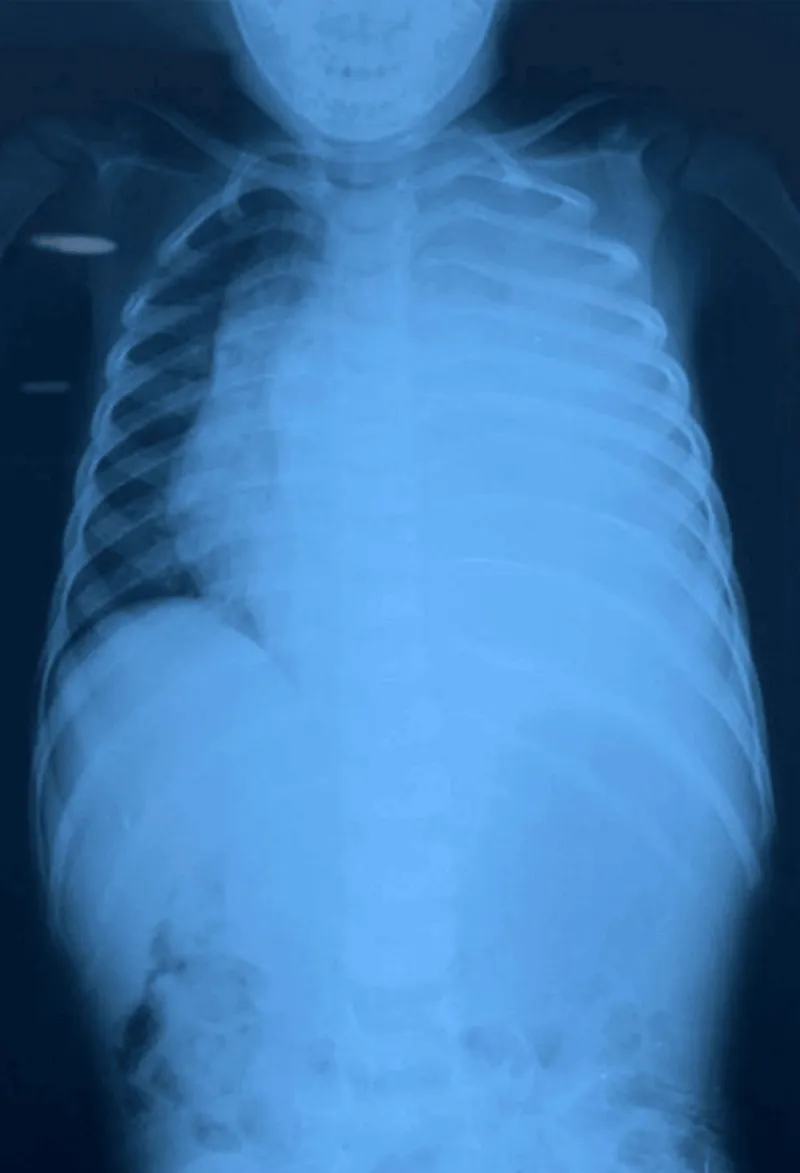

Despite treatment, the patient developed progressive respiratory distress. Contrast-enhanced thoracoabdominal computed tomography revealed a large prevertebral mass extending into the posterior mediastinum (Figure 2), raising strong suspicion for neuroblastoma.

Figure 2: Contrast-Enhanced Thoraco-Abdominal CT Scan.

(a) Axial CT section showing a large heterogeneous soft-tissue mass occupying the majority of the hemithorax and causing marked compression of the adjacent lung parenchyma. Only a small portion of aerated lung is visible laterally.

(b) Slightly inferior section demonstrating persistence of the mass with displacement of mediastinal structures and further compression of the ipsilateral lung.

(c) Lower thoracic section showing the inferior extension of the lesion, with partial visualization of compressed lung parenchyma and heterogeneous internal density of the mass.

(d) Most inferior section illustrating the continued presence of the mass with significant reduction of the aerated lung field and pronounced mass effect on surrounding thoracic structures.